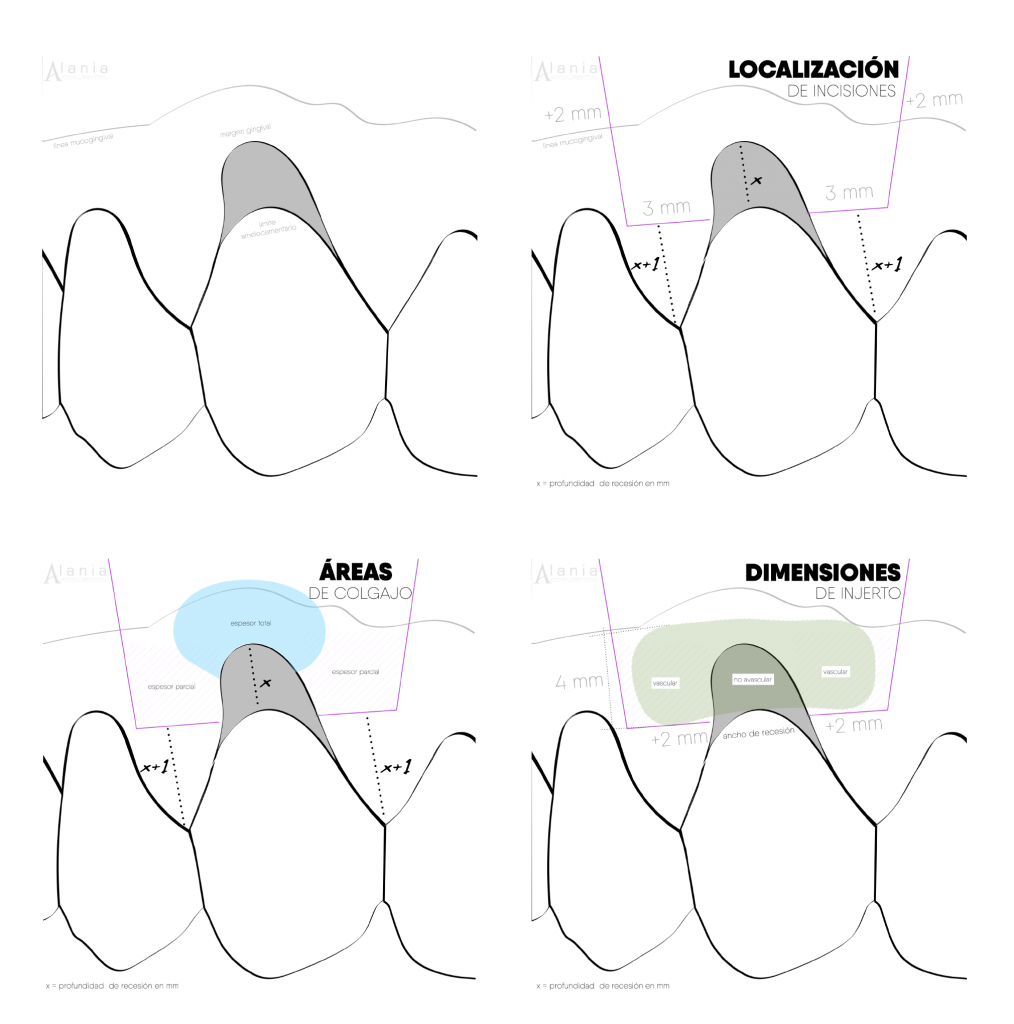

2. Elige una técnica de colgajo abierto

Uno de los puntos importantes es la liberación de la tensión, es más fácil si eliges una técnica que tenga incisiones de descarga (De Santics) en tu primera intervención, por consiguiente evita una recesión en la región estética.

Otro punto importante es que podrás ver en vivo y en directo: grosor del colgajo, periostio, las inserciones musculares, etc. Además, podrás comprender de mejor manera todo el conocimiento teórico que has acumulado engranándolo con lo práctico-clínico. Las técnicas de sobre o túnel ofrecen grandes ventajas sobre el proceso de cicatrización y dolor postoperatorio, pero requieren de un mayor entrenamiento en mi opinión.

4. Cuidado con la anatomía

Revisa el caso muchas veces, a pesar de que las técnicas tratan de describirse de la manera más detallada posible para ser estandarizadas y reproducibles en las manos de todos, podemos cometer algunos errores por: variantes anatómicas o no tener en consideración algunas referencias anatómicas.

Por ejemplo cuando operas un canino superior, muchas veces después de la línea mucogingival existe una depresión, es más la puedes sentir con tu dedo si tocas justo en el ángulo de la nariz; la literatura describe que las primeras incisiones para parcializar el colgajo son paralelas al diente, pero si sigues paralelo es muy probable que fenestres el colgajo y tengas que reprogramar tu cirugía, inventando una buena excusa con el paciente como:

De hecho dependiendo el tamaño de la fenestración esto puede ser real y ya no gracioso, por eso recuerda ir despacio y dar la angulación correcta según la anatomía del sitio que estas operando.

Paso a paso de Colgajo Desplazado Coronal + Injerto de Tejido Conjuntivo